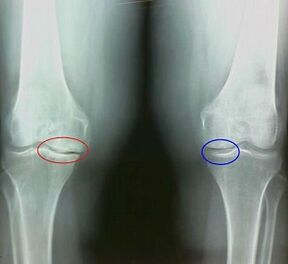

Was ist zum Beispiel der Unterschied zwischen Arthritis und Arthrose des Kniegelenks? Bei Arthritis tritt die Synovialschicht von Gelenkgeweben auf. Dies führt zu einer Erhöhung der Gelenktemperatur.

Die Artikulation nimmt zu, ein anhaltendes Schmerzsyndrom wird entwickelt, was während der Bewegung intensiviert wird. Bei Arthrose tritt der Schmerz erst nach körperlicher Aktivität auf.

Symptome: Was ist der Unterschied zwischen Arthritis und Arthrose?

Arthrose entwickelt sich allmählich und zeigt sich in den frühen Stadien nicht. Es wird oft durch körperliche Müdigkeit eingenommen. Die chronische Form der Arthrose wird auch als Osteoarthrose bezeichnet. Zur Frage, was schlimmer ist: Arthrose oder Arthrose, ist die Antwort offensichtlich. Die letzte Option ist eine Folge der Entwicklung einer Arthrose und ihrer akuten Form.

Unter den Symptomen einer Arthrose werden die folgenden unterscheiden:

- Die Schmerzen erscheinen nach körperlicher Aktivität, mit plötzlichen Bewegungen, Kurven, Neigungen, nach Ruhe, Schmerz vergehen;

- Eine charakteristische Krise wird in den Gelenken beobachtet;

- Die Schmerzen nach längerer Ruhe, die innerhalb von 15 bis 20 Minuten nach Mobilität auftritt (dies ist mit den stagnanten Phänomenen verbunden, die im Gelenk auftreten);

- Besorgt über den Schmerz von undurchsichtigen Nachtschmerzen, die aufgrund venöser Stagnation auftreten;

- Die entzündliche Form der Pathologie wird von Ödemen und Schmerzen begleitet;

- Die Artikulation ist deformiert, ihre Mobilität nimmt ab.

Wie Sie sehen können, sind die Unterschiede in den Symptomen unbedeutend: In beiden Fällen gibt es Schmerzen, Starrheit und Müdigkeit. Arthritis und Arthrose können unterschiedliche Gelenke im menschlichen Körper beeinflussen. Mit der Schädigung der Säule und der Bandscheiben entsteht Osteochondrose, sie ähnelt der Arthrose. Abhängig von der Krankheit wird die Arthrose des Knöchels, der Schulter, der Hüftgelenke usw. unterschieden.

Die Details der Symptome und der Differentialdiagnose tragen dazu bei, die Pathologie genau zu bestimmen: Arthritis oder Arthrose.